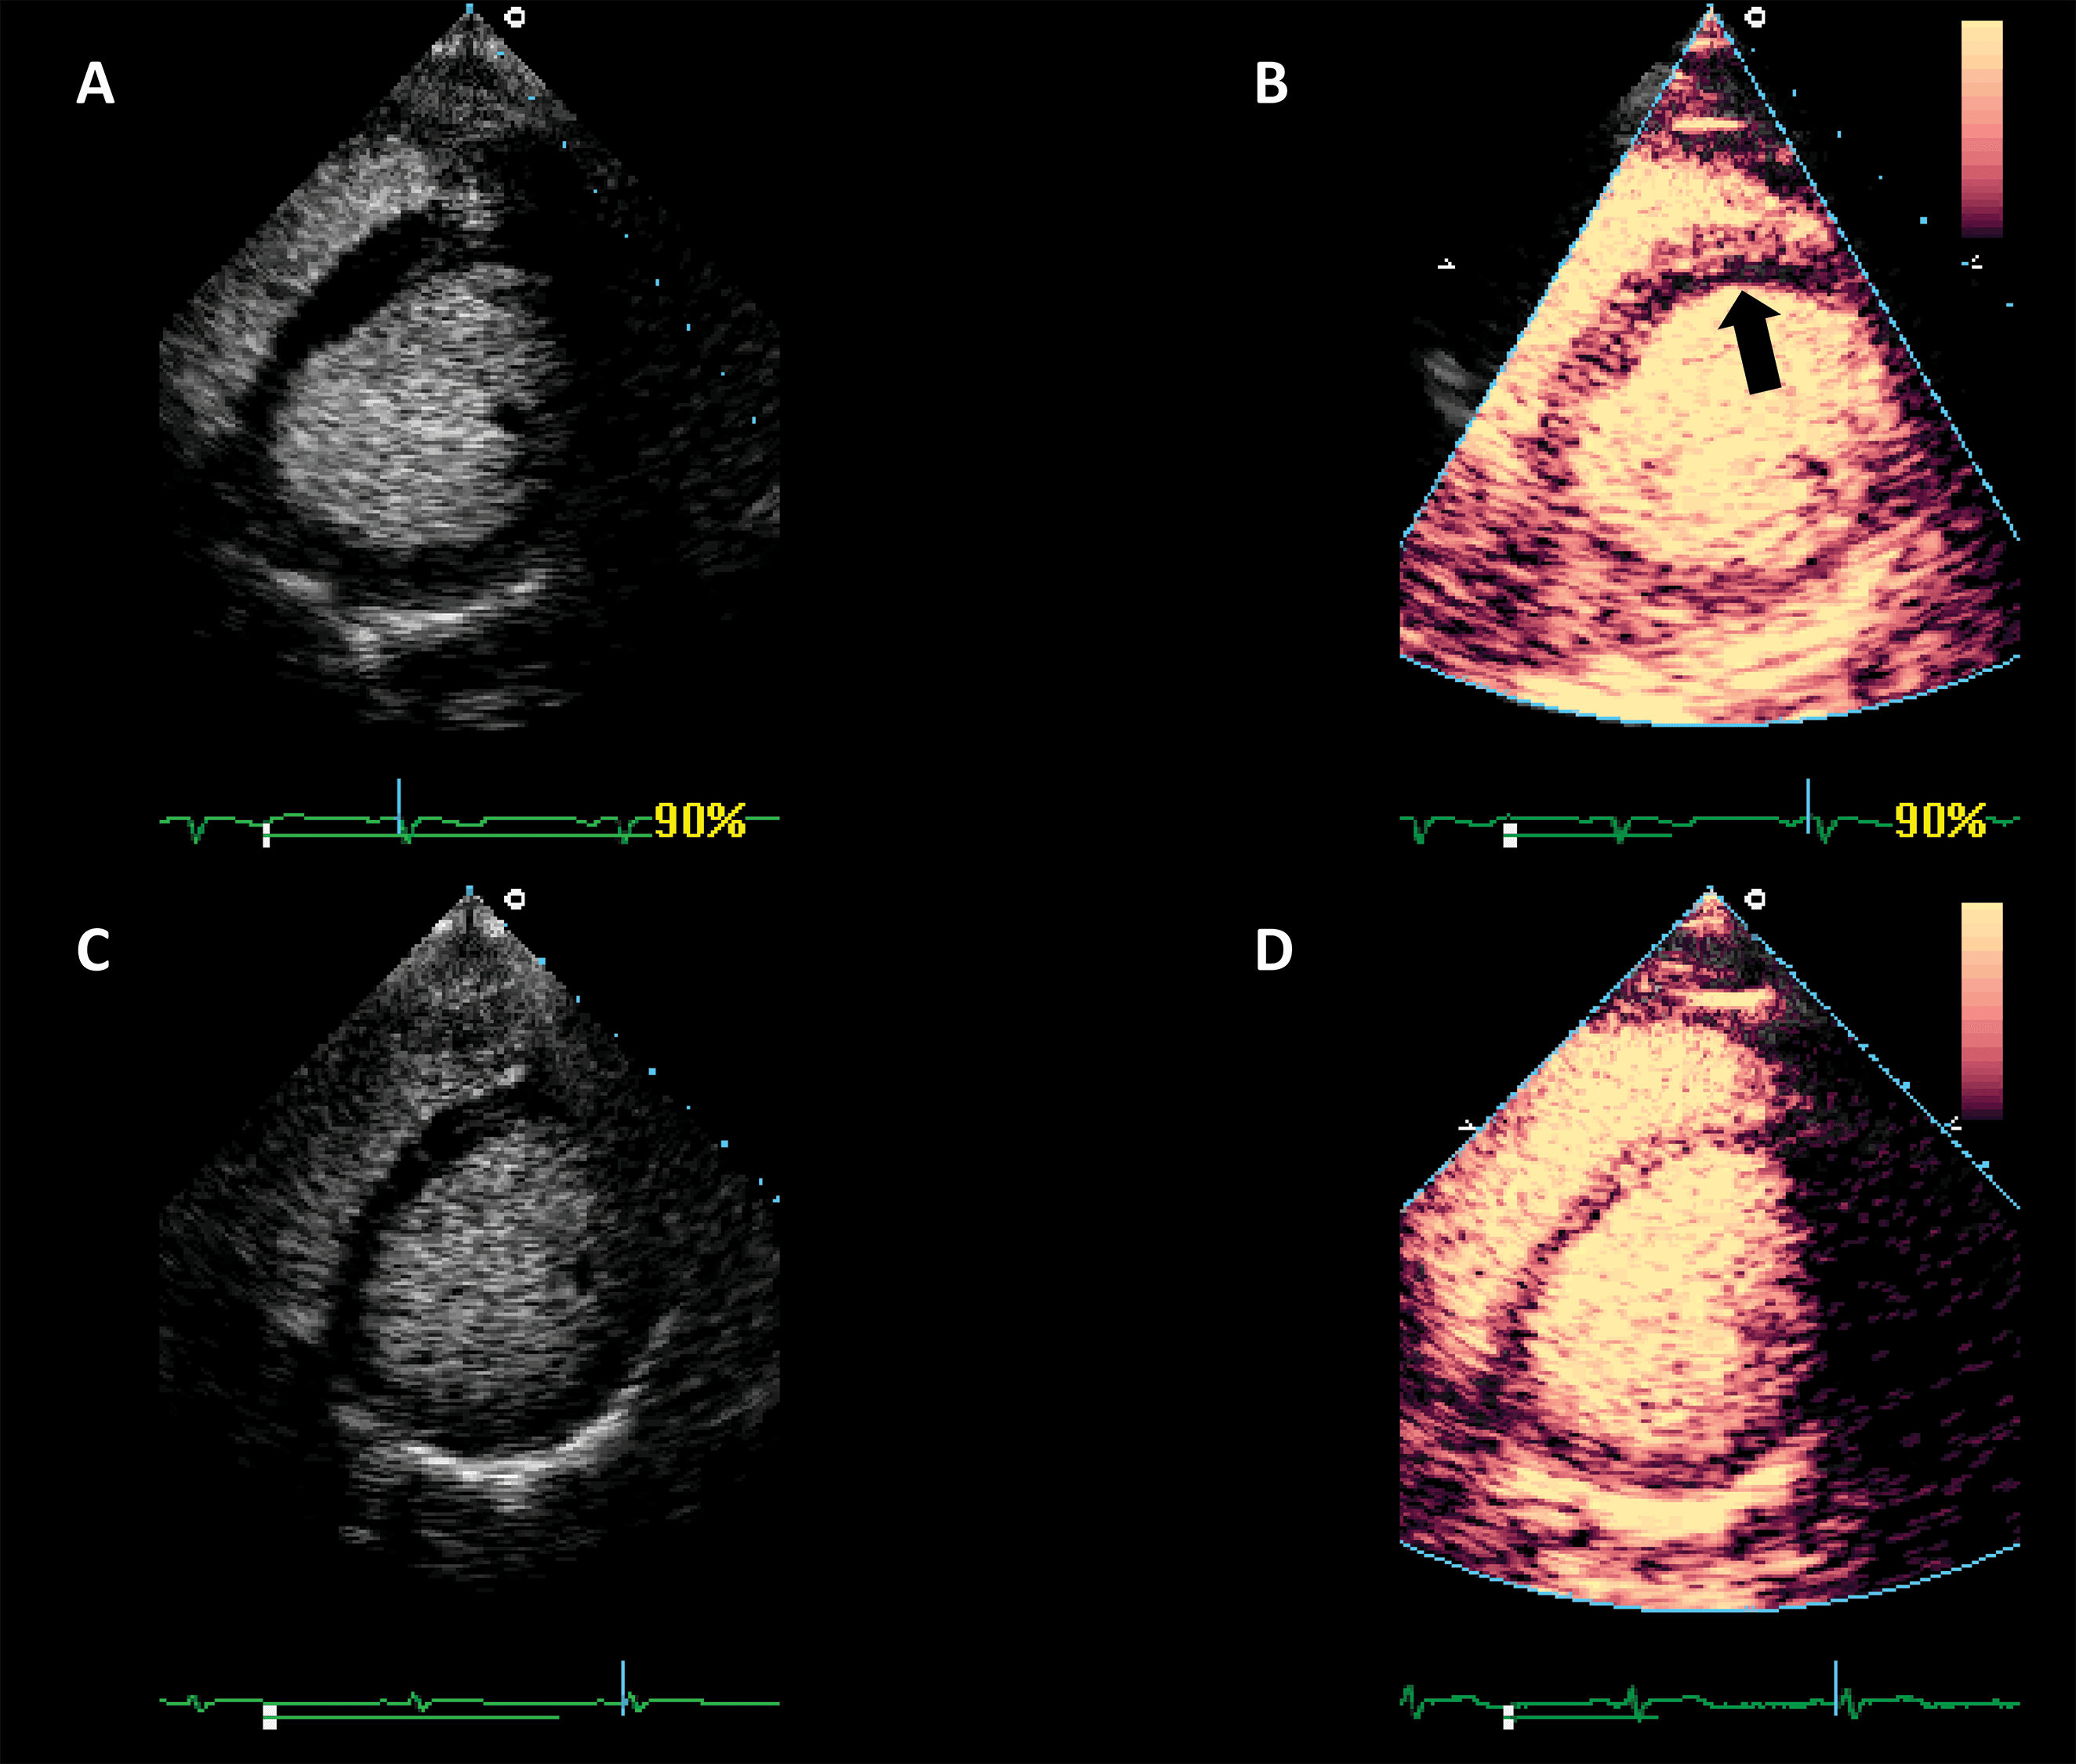

The addition of UEA during stress echocardiography protocols is usually achieved through an LVO application with low-MI harmonic imaging (Fig. 7, Video 6). The result is an increase in the likelihood of a diagnostic test, a better visualization of all myocardial segments, study quality and reader confidence, as compared to invasive or non-invasive reference [40, 41, 42, 43]. The addition of UEA to non-enhanced studies resulted in a better agreement with coronary angiography, even in patients with intermediate coronary lesions [44]. Of course, the use of LVO in stress echo has the largest impact in patients with suboptimal image [45]. Nevertheless, contrast-enhanced ultrasound also improves the wall motion score and detection of regional wall motion abnormalities in patients with adequate image quality [46]. Contrast-enhanced dobutamine stress echocardiography provided adequate risk stratification in patients with increased cardiovascular risk due to obesity or suspected coronary artery disease [47, 48, 49].

Fig. 7.Microbubble enhanced stress echocardiography. Baseline non-enhanced images are recorded in apical 4 and 2 chambers (A,B), demonstrating insufficient delineation of the endocardial borders; With contrast (C,D) the LV contours become clearly visible. Source: personal collection.

In patients with incomplete visualization of at least 2 contiguous segments contrast should be used for stress echocardiography. In patients with adequate image quality, contrast could be used to assess the myocardial perfusion, in addition to wall motion [7, 13].